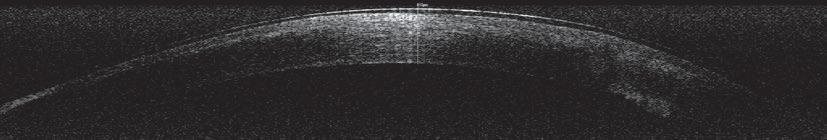

Al mencionar las aplicaciones más frecuentes de la ecocardiografía en el campo de la anestesiología, Xavi Navarro se centró en la evaluación preanestésica, así como en la de la volemia y la respuesta a fluidos.

Ecografía aplicada a la evaluación cardiaca y hemodinámica en anestesia

Xavi Navarro también remarcó el trabajo multidisciplinar, destacando la labor realizada conjuntamente por cardiólogos y anestesiólogos, y comentó que la ecografía permite realizar una evaluación rápida, a tiempo real y no invasiva de la estructura y función cardiacas, de manera que se pueden optimizar la seguridad y el manejo cardiovascular del paciente.

Entre sus limitaciones, hizo hincapié en la necesidad de tiempo para su aprendizaje, y mencionó también el coste, la posibilidad de encontrar hallazgos inespecíficos y la necesidad de realizar estudios que validen su uso y precisión, entre otras.

Al mencionar sus aplicaciones más frecuentes en el campo de la anestesiología, se centró en la evaluación preanestésica y en la de la volemia y la respuesta a fluidos, aunque también hizo referencia a la monitorización hemodinámica durante la anestesia y durante la recuperación, así como a la detección de complicaciones intra y posoperatorias:

• Con respecto a la evaluación preanestésica, recomendó realizarla a animales de razas predispuestas a las cardiopatías, así como a los sénior o a los que tengan signos clínicos que sugieran enfermedad avanzada. No obstante, puesto que “hay que tener cuidado con los pacientes asintomáticos y con los gatos”, en general recomendó realizar un estudio ecocardiográfico siempre que sea posible.

• Al hablar de la evaluación de la volemia y la respuesta a fluidos, Navarro comentó que no existen “normas” para el uso clínico de la administración de fluidos intravenosos para la optimización del gasto cardiaco y la perfusión tisular. En

todo caso, y puesto que el aumento de la precarga no siempre es necesario ni es bien tolerado, se recomienda un enfoque individualizado para cada paciente y la respuesta positiva del animal se podrá evaluar gracias al uso de marcadores, tanto estáticos como dinámicos.